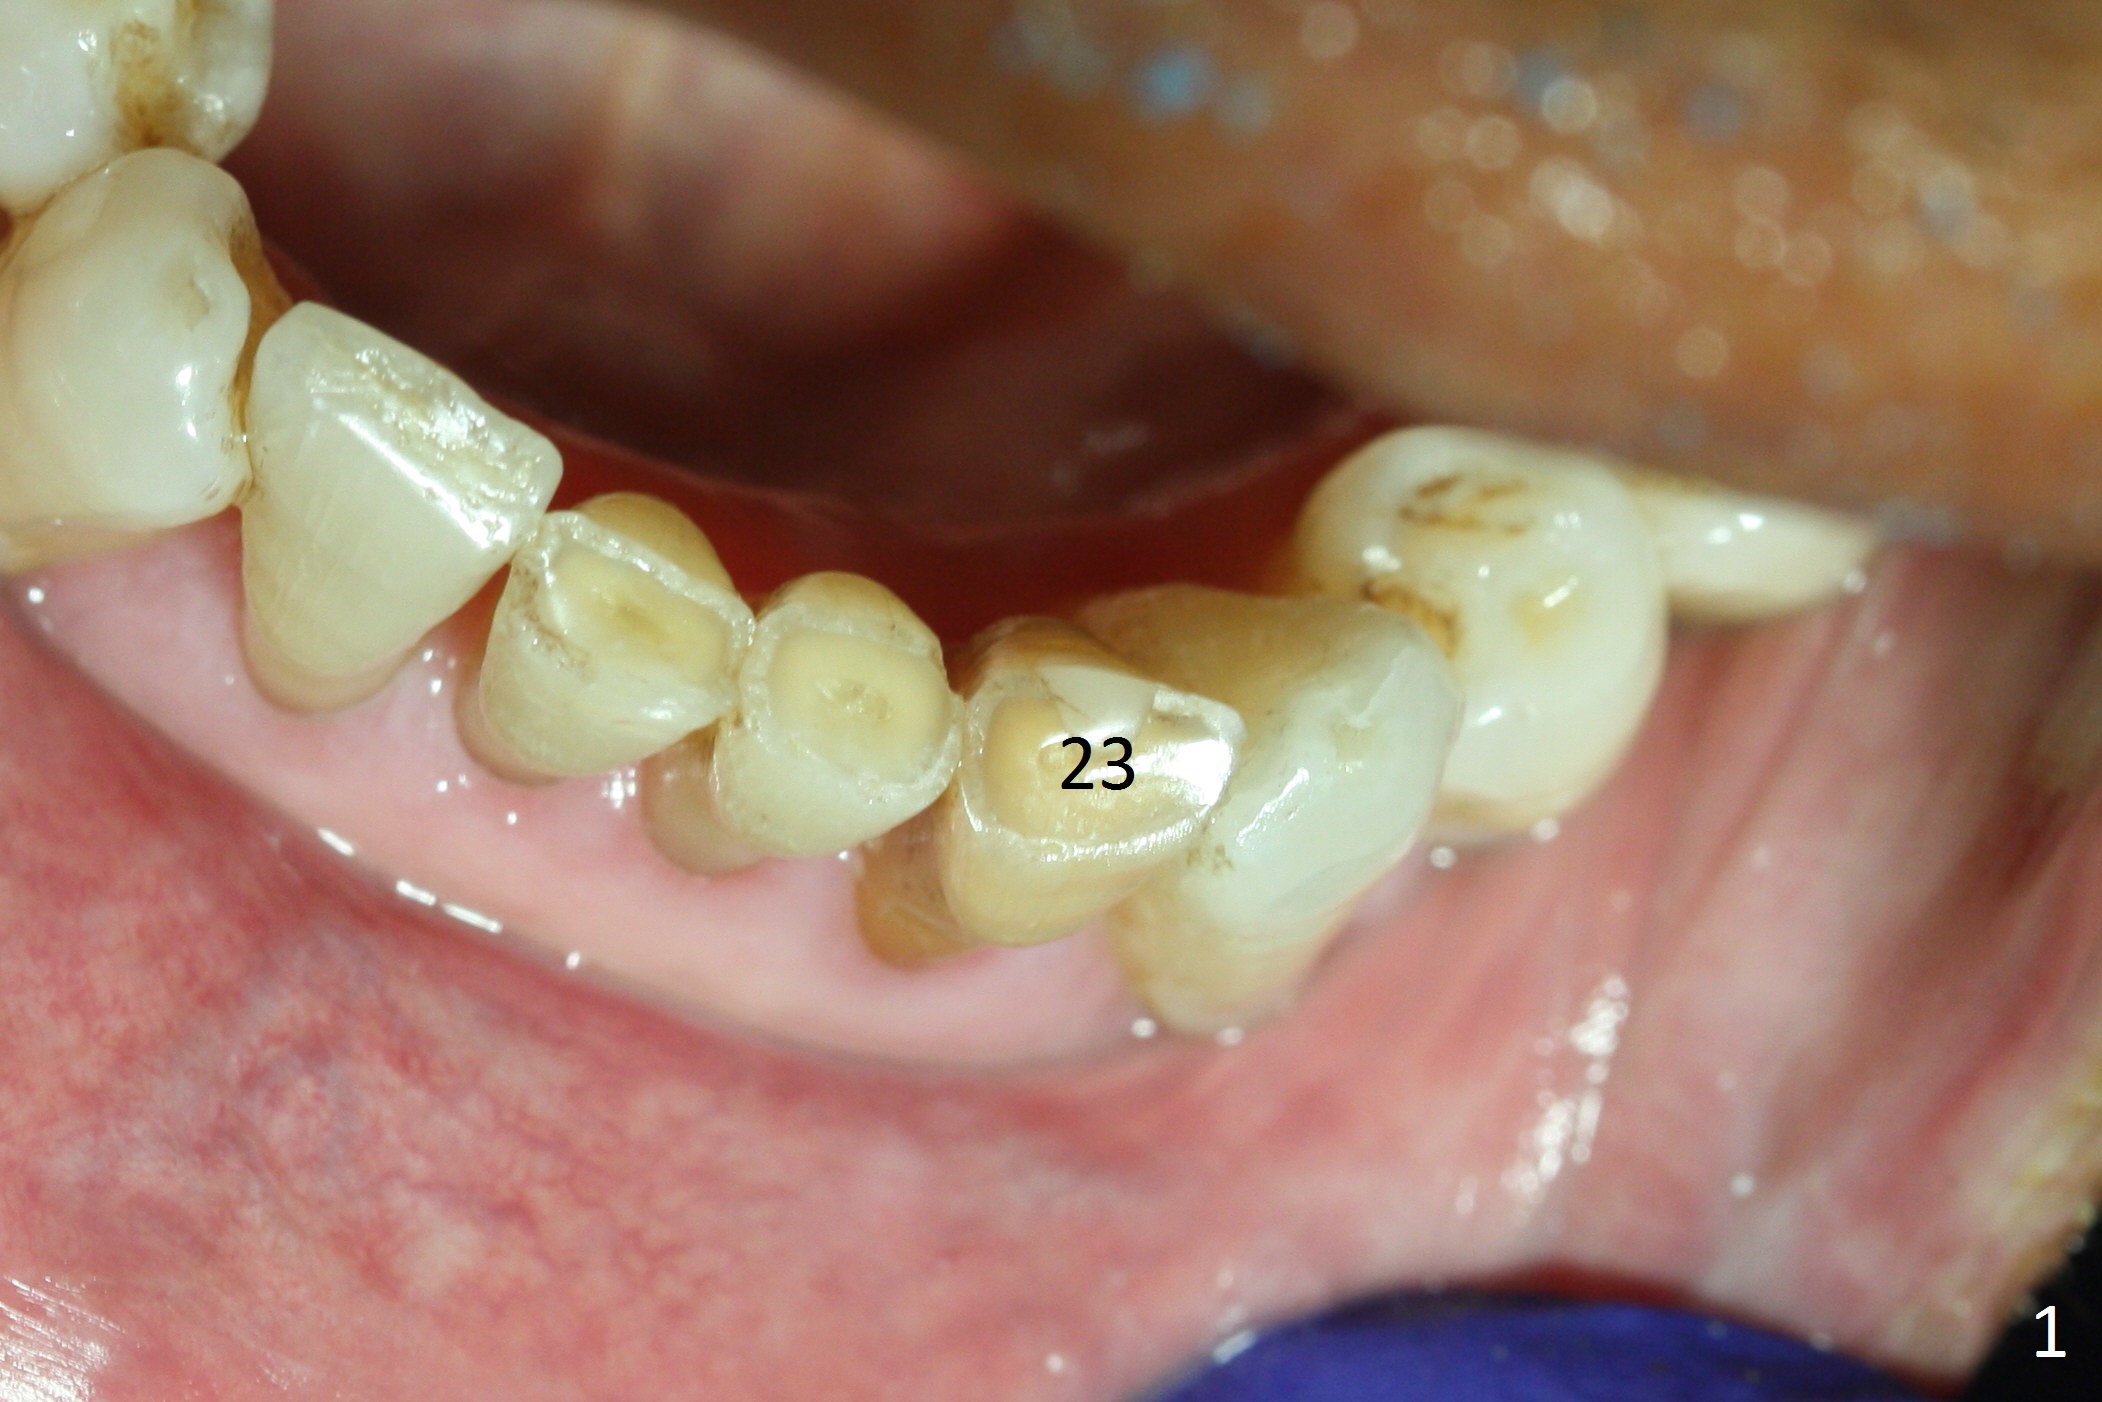

The tooth #23 is going to be extracted because the patient cannot masticate normally with mobility (Fit.1). The gingival depth is measured 2-4 mm after extraction. The 1st intraop PA taken with 1.2 mm drill for 16 mm shows the mesiodistal width is 5.11 mm (Fig.2); a 2.5x14(2) mm 1-piece implant is placed with >35 Ncm (Fig.3 with allograft placed). Following abutment preparation, an immediate provisional is fabricated to close the socket (Fig.4 P). There is no bone loss (Fig.5) or gingival inflammation (Fig.6 after reprep) 3 months postop. The narrow implant (2.5 or 2.0 mm) is indicated in the narrow edentulous space. The distal crest seems to be reduced in density and lower in height 1 year 7 months (Fig.7) and 1 year 11 months (Fig.8) post cementation. The severity does not worsen probably related to use of water pik. The crown looks bulky probably due to too large the abutment and too buccal placement of the implant (Fig.9, 10, as compared to Fig.1). A 2 mm implant may help?